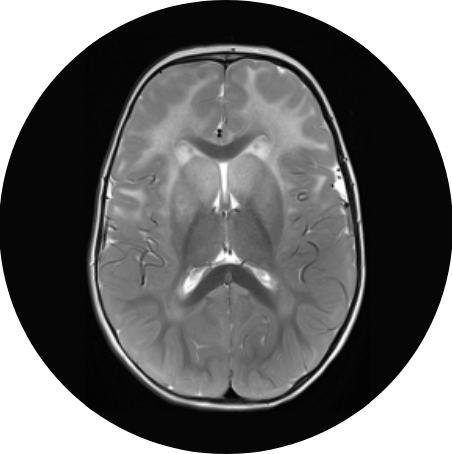

Neurologistsspecialists in disorders of the nervous system—use their expertise to diagnose and treat rare conditions like Alexander disease. Through detailed clinical exams, medical imaging such as a brain MRI (magnetic resonance imaging) and genetic testing, neurologists can piece together the clues that lead to an accurate diagnosis and management plan.

Brain MRI

MRI image of a brain.

MRI is a painless test that produces detailed pictures of the brain, helping neurologists identify signs of Alexander disease.